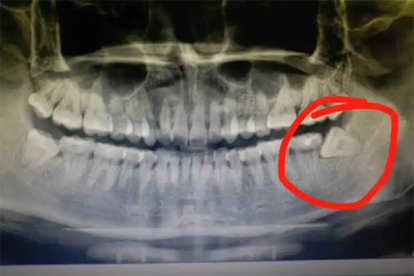

下午一般可以拔智齿,但需结合口腔状况和医生评估决定。拔智齿的时间选择主要取决于术前准备、术后护理条件及个人耐受度。

上午拔牙的优势在于患者经过夜间休息后身体状态较好,且术后有充足时间观察出血等反应。但下午拔牙同样可行,尤其是对于非复杂智齿、无全身性疾病且术后能保证充分休息的人群。术前需避免空腹或过饱,确保血压、血糖稳定。若智齿位置正、无急性炎症,下午拔除后遵医嘱冷敷、避免剧烈活动,通常不影响恢复。

少数情况下如下午就诊时间紧张、患者存在高血压或糖尿病未控制、智齿埋伏较深伴发感染时,医生可能建议改期至上午操作。这类情况需优先控制基础疾病,并预留足够术后观察时间。